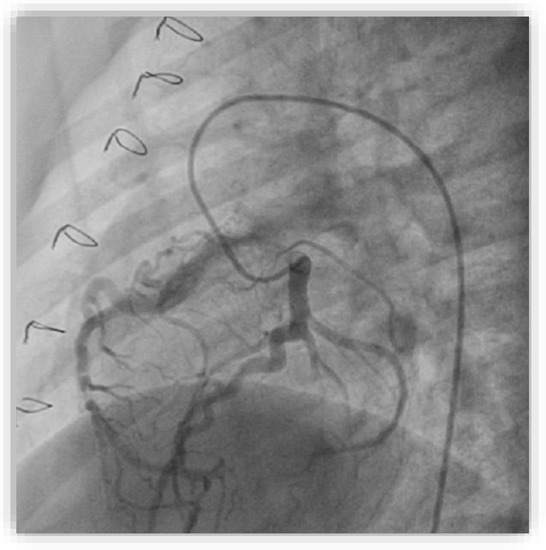

Anomalous origin of the right coronary artery from the pulmonary artery (ARCAPA) is a rare congenital coronary anomaly, with an uncertain prevalence and often diagnosed incidentally. This case report presents a 62-year-old male with ARCAPA diagnosed during an evaluation for chest surgery. The patient had a history of colon cancer and active tuberculosis, complicating the clinical management. He reported chest pain, shortness of breath, and palpitations, with atrial fibrillation observed on a 24 h Holter ECG. Coronary angiography revealed robust collateral circulation and a suspected anomalous origin of the right coronary artery, confirmed by CT imaging. The patient’s stress MRI showed mildly reduced left and right ventricular ejection fractions and perfusion deficits in the apical segments (2/17) of the septal and inferior walls. Given the patient’s comorbidities, including active tuberculosis, the Heart team decided on a non-operative management approach, focusing on careful monitoring and pharmacological management rather than immediate surgery. This case emphasizes the complexity of managing ARCAPA in the context of significant comorbidities, highlighting the importance of individualized, multidisciplinary treatment strategies. Early diagnosis using advanced imaging techniques is crucial, and a non-operative approach can be considered in patients with preserved left ventricular function and no significant ischemia, as demonstrated in this case. Full article

Show Figures

Figure 1